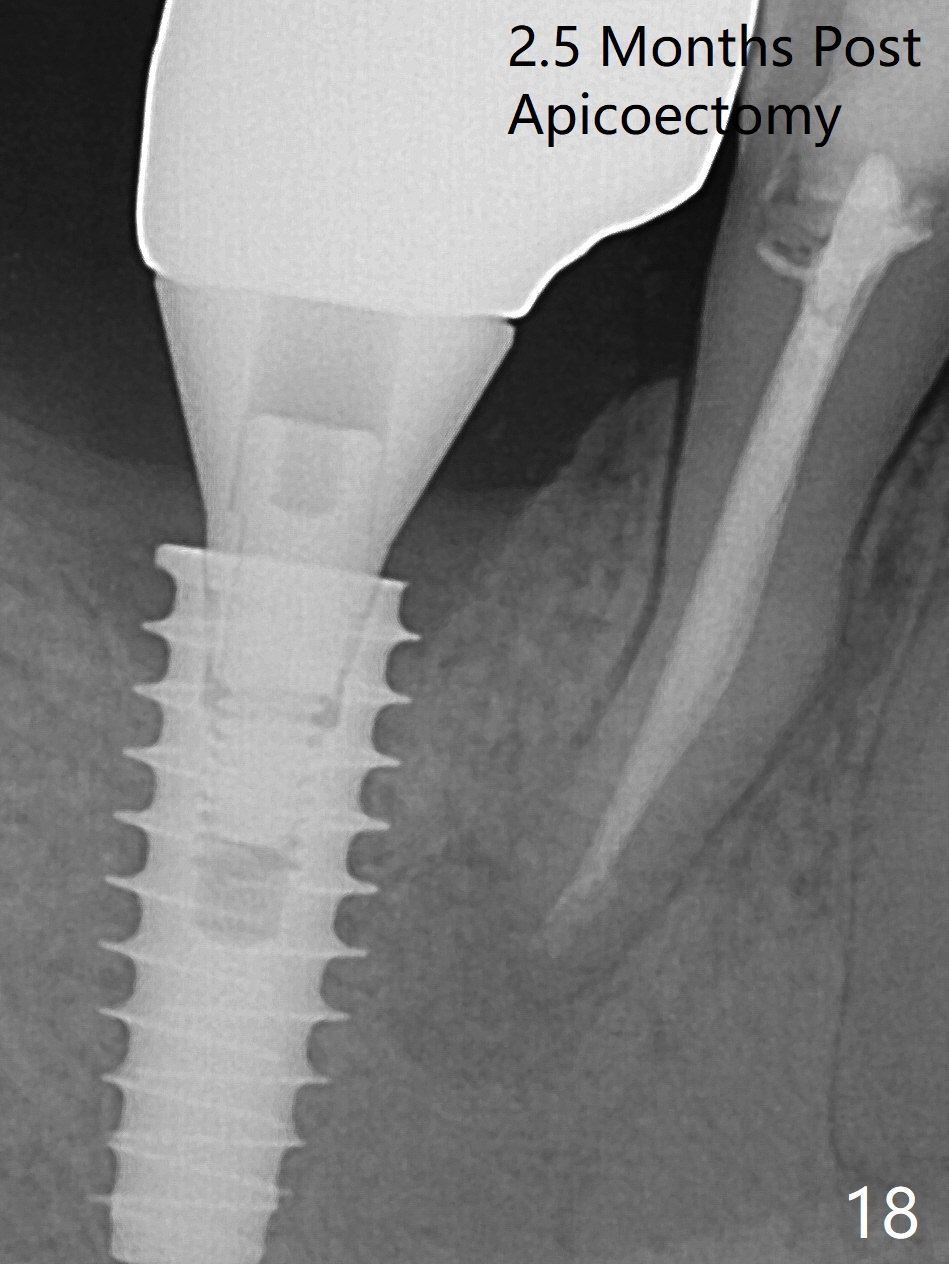

Bone graft seems to sink down and becomes denser 3 months postop (Fig.6 arrow). The bone continues being denser 5 months postop (Fig.7). There is periapical radiolucency of the tooth #29 (^). RCT is done (Fig.8). The pain persists 2 weeks postop (Fig.9,10). There is no missing canal (Fig.9). The apex is close to the implant (Fig.9 *). Apicoectomy will be performed if needed. It appears that the implant is also placed buccal (Fig.10 <) and/or the implant too large for the site. Therefore there should be a 2-3 mm buccal gap before and after implant placement. Separation and reflection of the buccal flap allows better visibility. The pain persists 1 month post RCT and 6 months post implant placement. RCT retreatment is initiated (Fig.11,12) with placement of Calcium Hydroxide paste after redebridement with 30/.04 rotary file at 23.5 mm (.5 mm longer than the earlier RCT, Fig.13). RCT retreatment finishes with apparent transportation and extrusion in 4 weeks (Fig.14,15), followed by apicoetomy (Fig.16,17) (20 days later)). Discomfort remains 2.5 months postop (Fig.18). Keep watching.